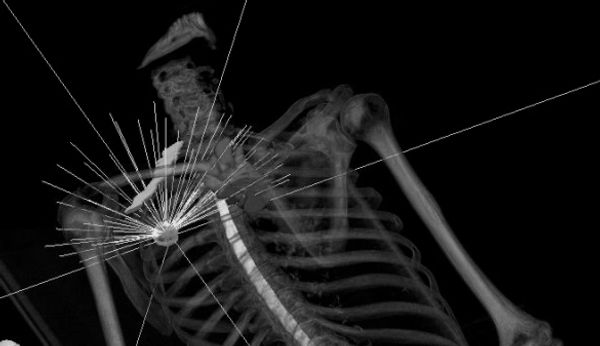

We offer comprehensive medical physics services in: